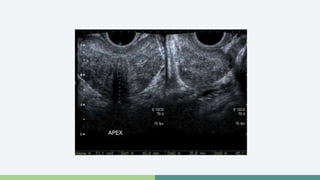

Próstata normal

• Vista longitudinal

Ultrasonografía • TRUSse realiza después de un DRE anormal o PSA elevado • Biopsias • Lesiones hipoecoicas (60-70%) • Lesiones hiperecoicas (30-40%)

Próstata normal •Vista longitudinal